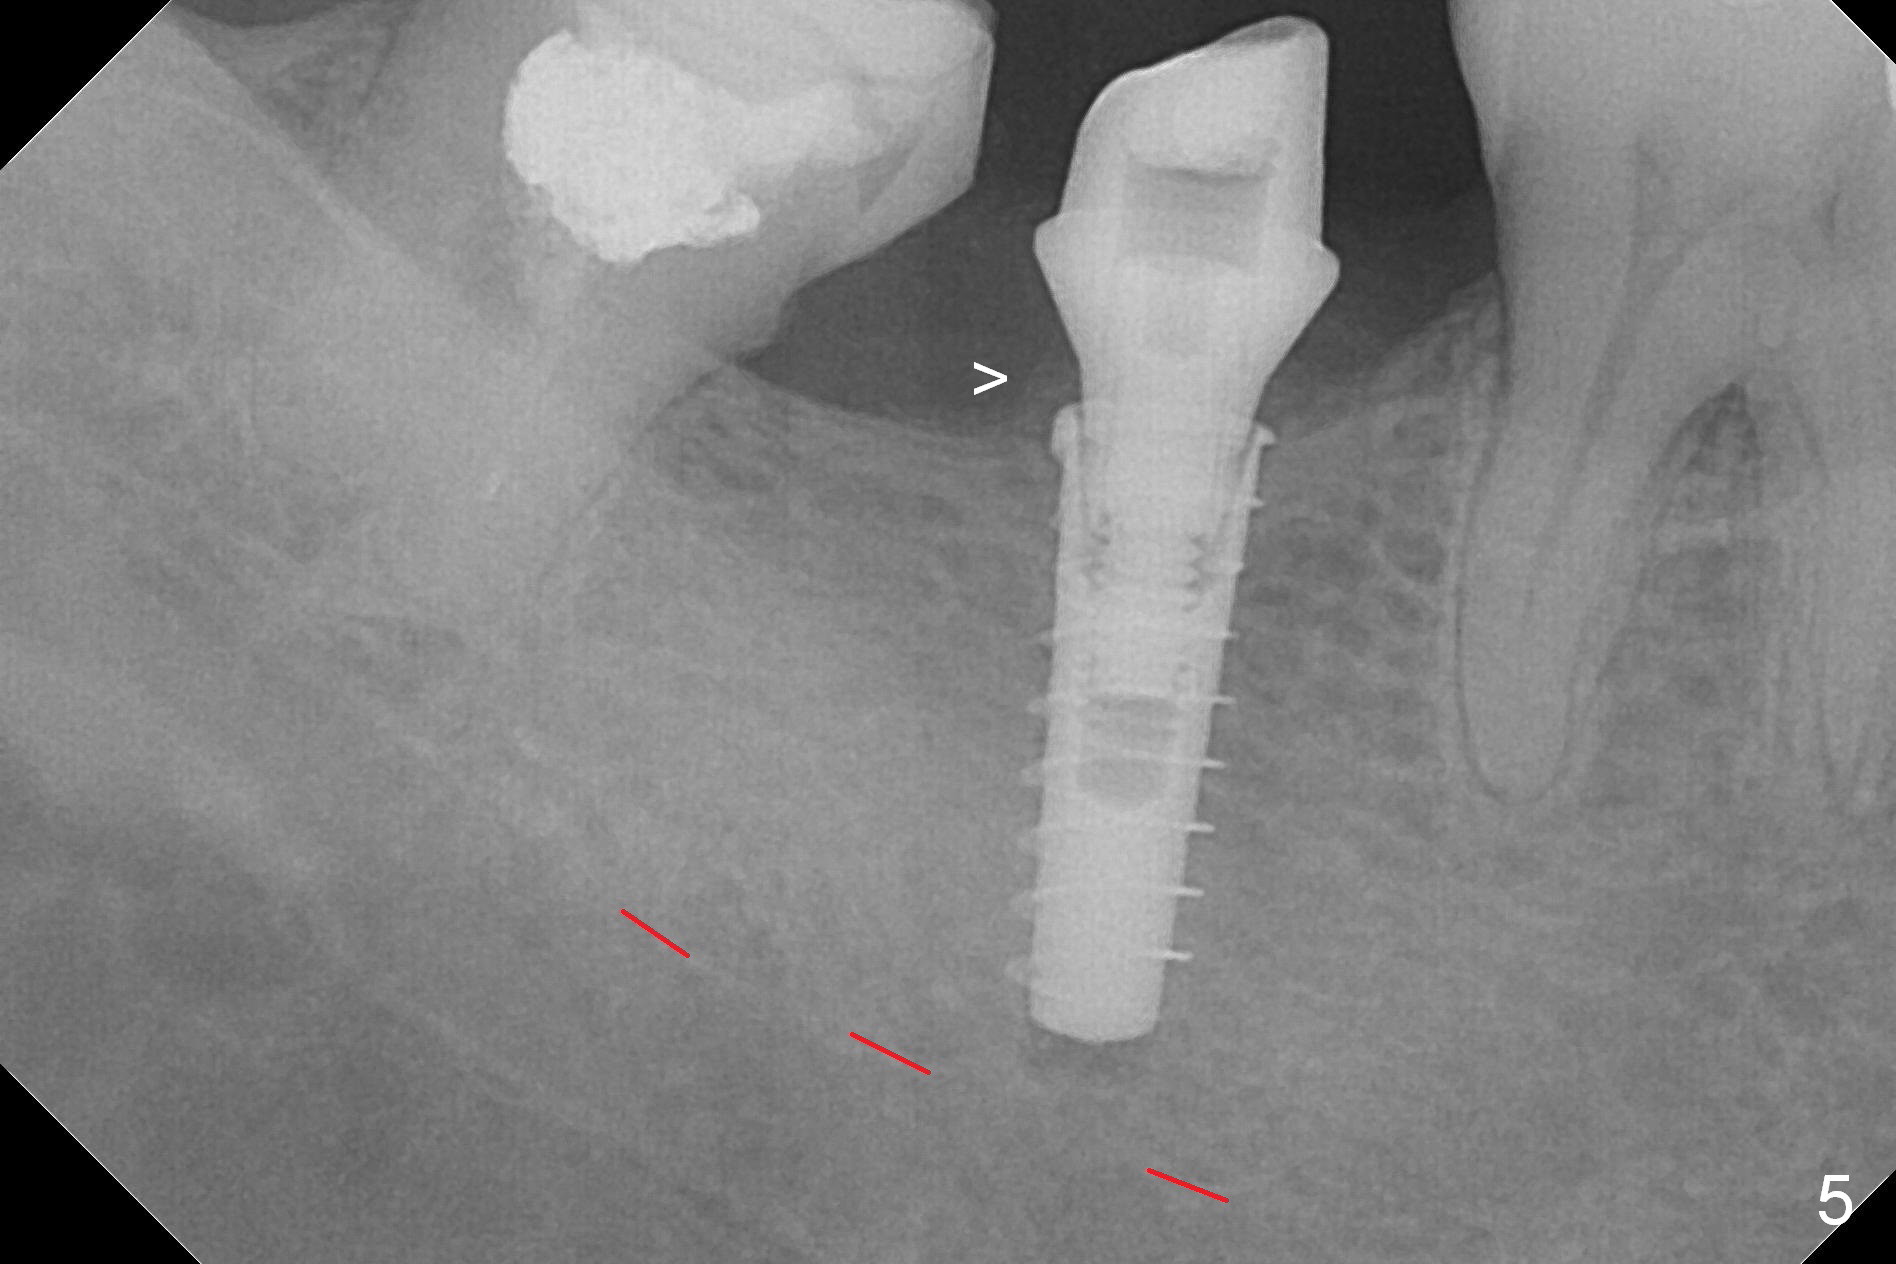

The ridge at #31 is also narrow buccolingually (Fig.1 *).  After incision and 1.6 mm pilot drill, a guide pin with 7 mm length is inserted to confirm trajectory and depth; it appears that 11 mm osteotomy has enough clearance from the superior border of the Inferior Alveolar Canal (IAC, Fig.2 red dashed line).  Following Marking Bur, 3.3 mm Magic Drill and final drill, the buccal plate seems to be thin (Fig.3 *).  When a 4x11 mm IBS implant and 5x4(2) mm pair abutment are placed, the distal thread is exposed (Fig.4 >), the abutment contacts the opposing tooth (data not shown) and there is 2.7 mm clearance from IAC.  After increasing the osteotomy 1-2 mm, the implant is placed deeper; the autogenous bone with Osteogen is placed around the plateau of the implant (Fig.5 >), particularly buccally, followed by collagen membrane.  When sutures are placed around the abutment, the buccal ridge looks bulkier (Fig.6) than preop (Fig.1).  It may remains so long term.  The flap surgery makes it possible for simultaneous GBR and reduction in possibility of peri-implantitis.  Last, periodontal dressing is applied.